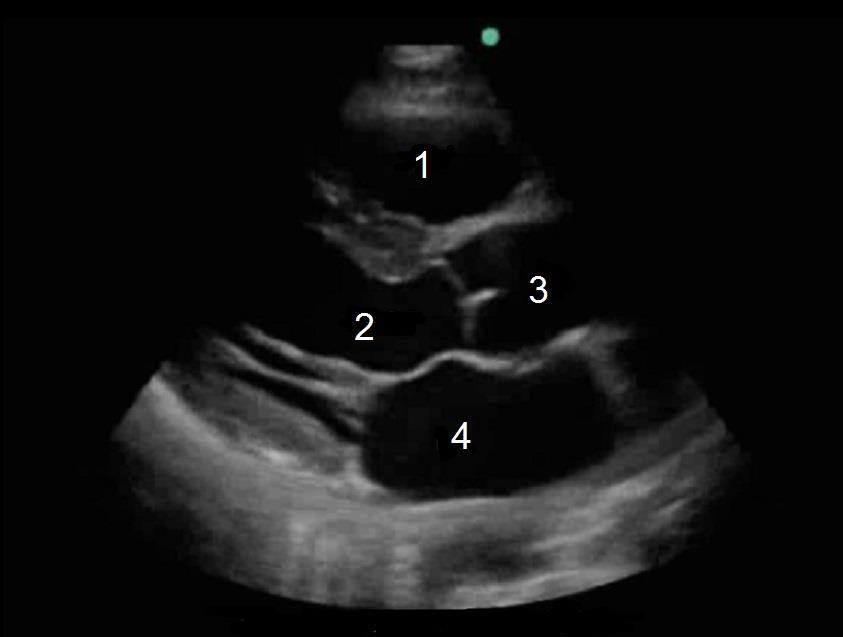

Heart Parasternal Long Axis (PLAX) in Diastolic Image

1. Right Ventricle (RV)

2. Left Ventricular Outflow Tract (LVOT)

3. Aorta

4. Left Atrium (LA)